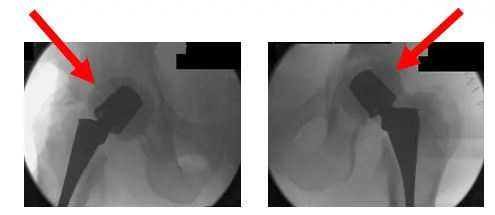

El Sr. LR es un caballero de 53 años que, por desgracia, desarrolló cambios artrósicos en la cadera derecha a una edad relativamente temprana. Fue atendido por un cirujano ortopédico en una institución diferente aproximadamente 10 años antes de que lo atendiera yo, y...

El paciente es un varón de 55 años que acudió a nosotros quejándose de luxación recurrente de prótesis de cadera derecha. El paciente declaró que esto había estado ocurriendo desde que tuvo una artroplastia total de cadera derecha (THA) hace unos años realizada en una...